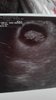

A powyżej moja fasolka.

Z usg widać 6t2d chyba ;p